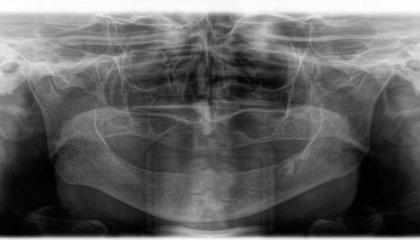

Before